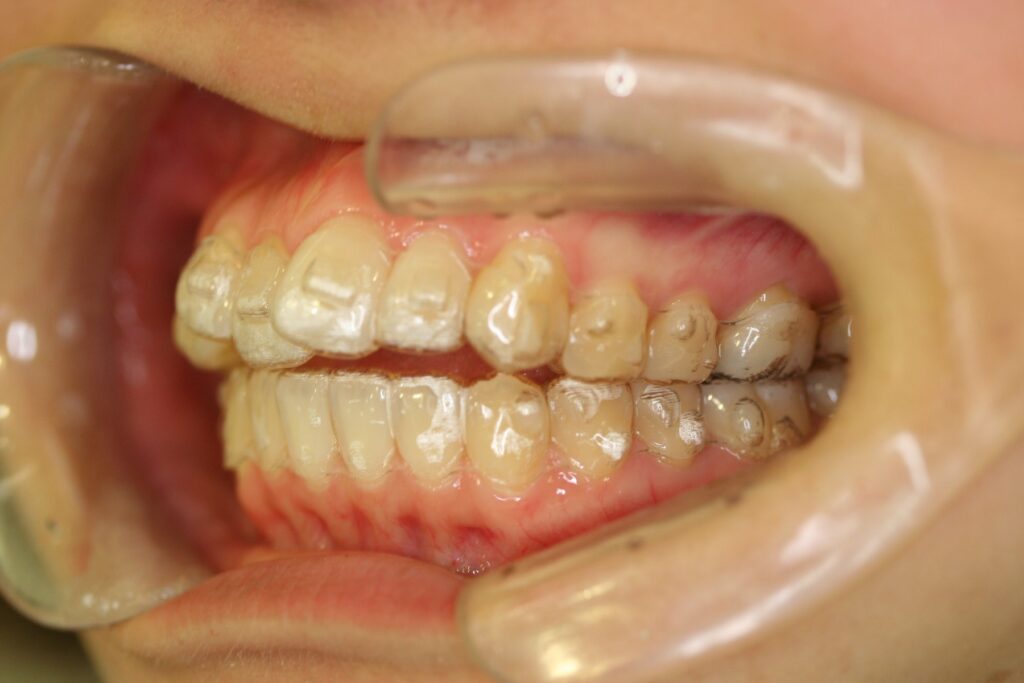

治療実績(症例) アライナー矯正 症例1 上顎前突症例 症例2 上下顎前突症例 症例3 叢生 症例4 開咬 症例5 開咬(外科的矯正治療) アライナー矯正 Post Share Hatena Line RSS feedly Pin it note 1.主訴2.診断名3.初診時年齢4.治療に用いた主な装置とオプション5.抜歯部位6.治療期間・通院回数7.総額と費用内訳総額相談検査・診断料調整料4,000円8.リスク・副作用 治療前 治療中 治療後